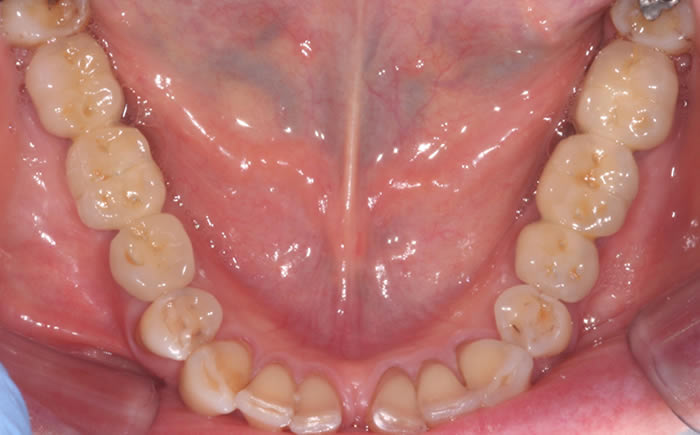

Gum disease

Case Two (2 images)

Treatment of moderate gum disease.